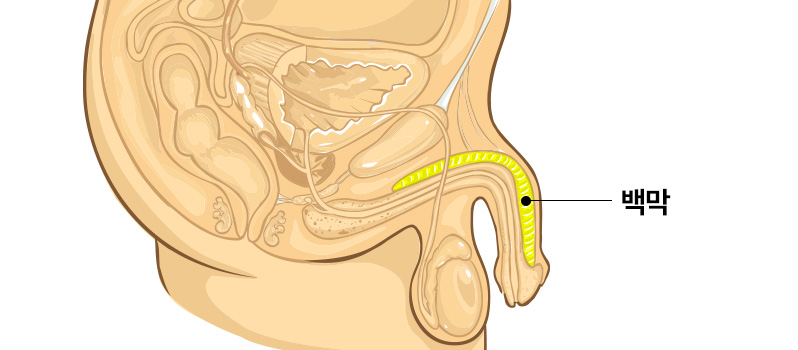

자라고추

성기 백막의 인장력이 강해

마치 자라의 ‘목’ 처럼

성기가 몸 안쪽으로 숨는 경우

수술방법

이식재 삽입, 백막고정을 통한 무게추 및

지지효과로 성기 매몰증상 억제

*확대수술을 통해 2~4cm 길이연장 가능